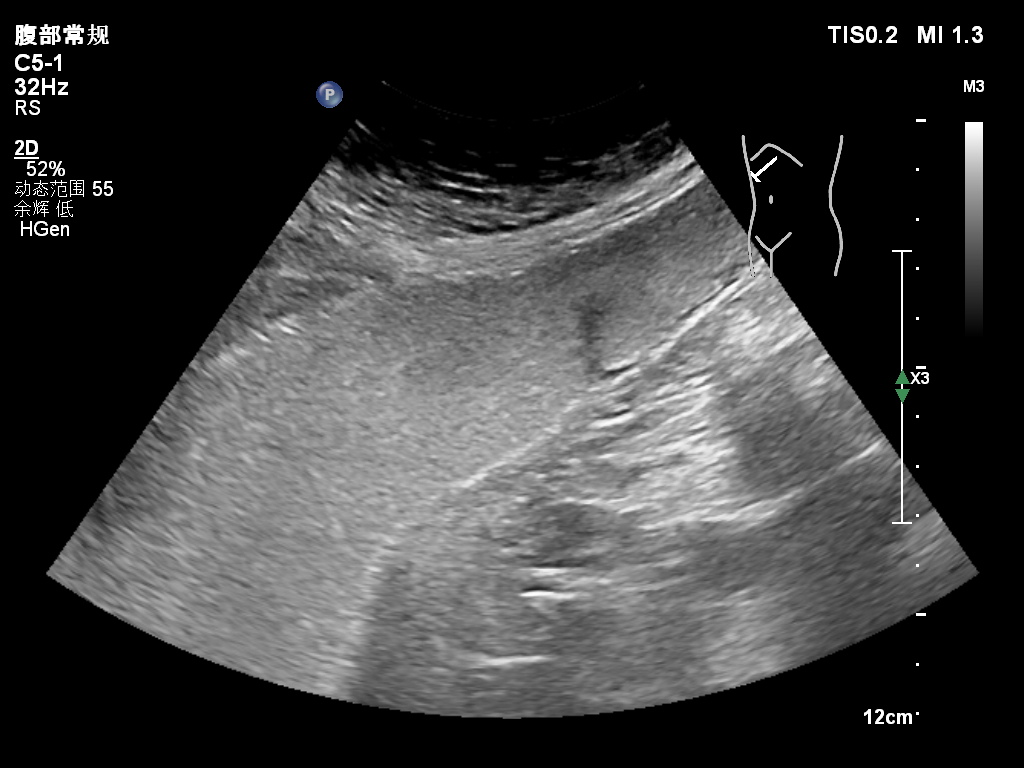

胃息肉